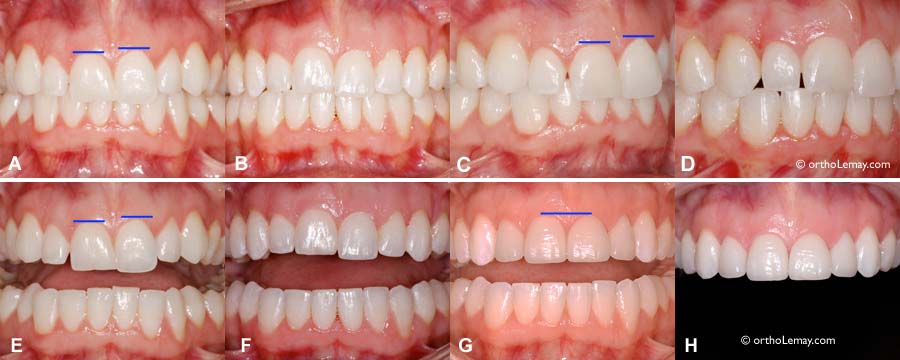

#2 Variation de l’esthétique du sourire chez la même personne que les images en #1 ci-dessus. (A et B) 8 images différentes du sourire d’une jeune femme. Selon le “stage” du sourire, les lèvres sont positionnées différemment et dégagent inégalement les dents en hauteur et des deux côtés de la bouche. Ainsi, selon la position des lèvres, le sourire est asymétrique et peut donner l’impression que ce sont les dents ou le plan occlusal qui sont croches. (B) La différence pour les 4 photos du bas est que les incisives latérales ont été modifiées légèrement avec de la cire blanche pour simuler un allongement de ces dents afin de montrer à la patiente l’effet que cela pourrait sur son sourire avoir si elle faisait allonger ces dents avec du composite